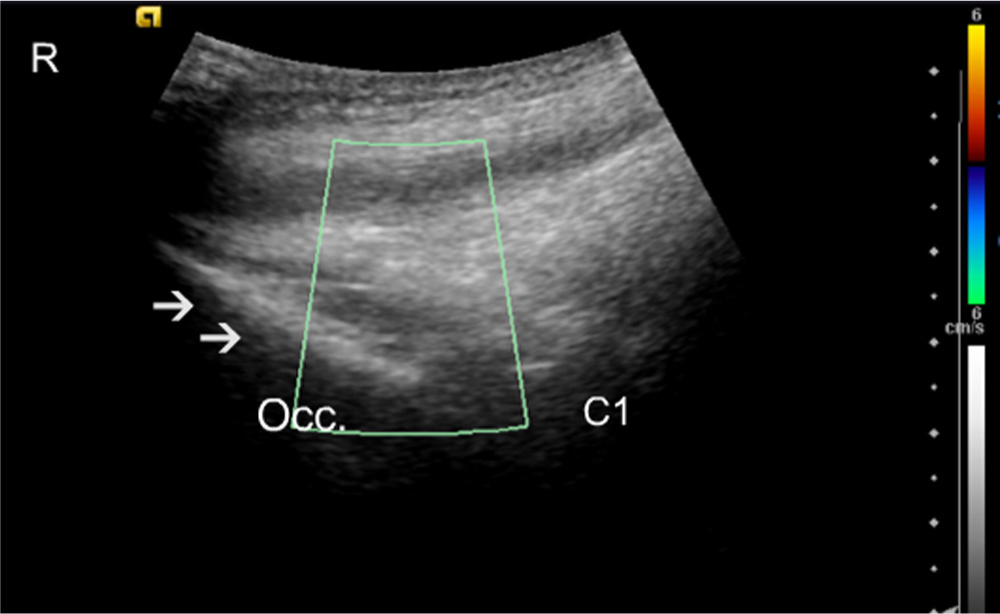

Control subject longitudinal midline. Colour Doppler scan. The C1 area is shown with no apparent blood vessels. Arrows identify the occipital bone (Occ.). R, rostral.

It was not possible to visualize the origin of the blood vessels exactly; however, in the suboccipital region, the high blood flow corresponded to the insertion of the semispinalis capitis and the rectus capitis posterior minor muscles. At the C1 level the high blood flow was more pronounced at the posterior tubercle, corresponding to the insertion of the rectus capitis posterior minor muscles (Figs. 1, Fig. 2, Fig. 3, 4). At the C2 level the high blood flow was found in the region of the spinous process, corresponding to the origin of the rectus capitis posterior major and the obliquus capitis inferior muscles, and bilaterally juxtapositioned to the facet joints (Figs. 5, Fig. 6, 7).